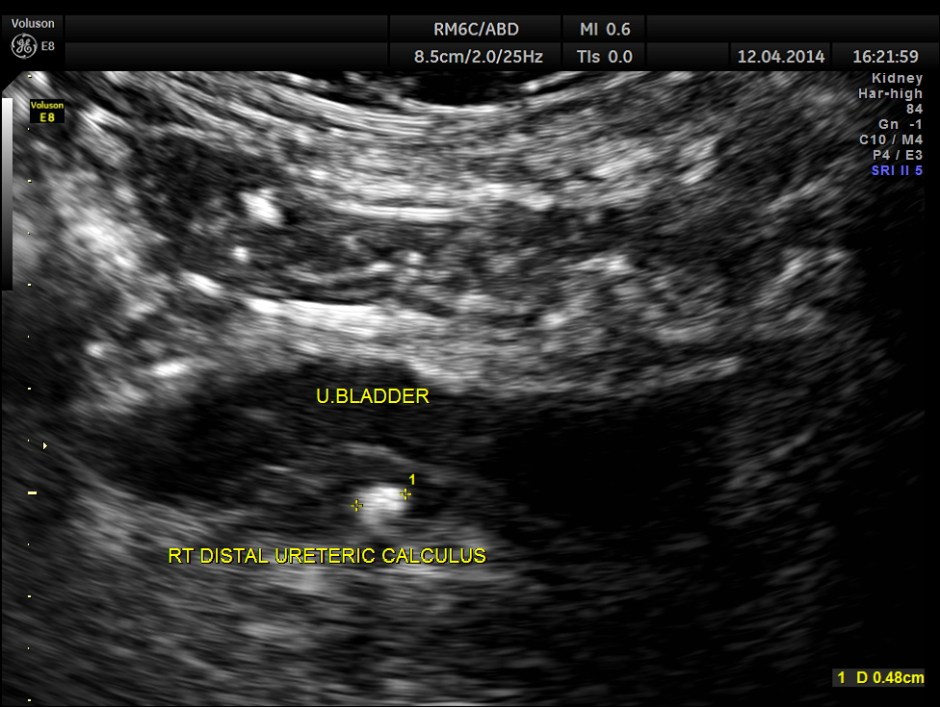

Post void bladder was studied and showed the following .

Lo and behold – a distal right ureteric calculus is clearly seen now .

Usually we pick up all ureteric calculi and distal ureteric pathologies with a full bladder . Usually distal ureteric calculus will cause some amount of obstructive features in the ureter and the kidney . That was also absent in this patient .

But occasionally like this patient , the distal ureters can be compressed with a full bladder and such findings could be missed unless we do a post void study, especially when they have a LUTS symptoms . In this patient the bladder wall also showed mild thickening.